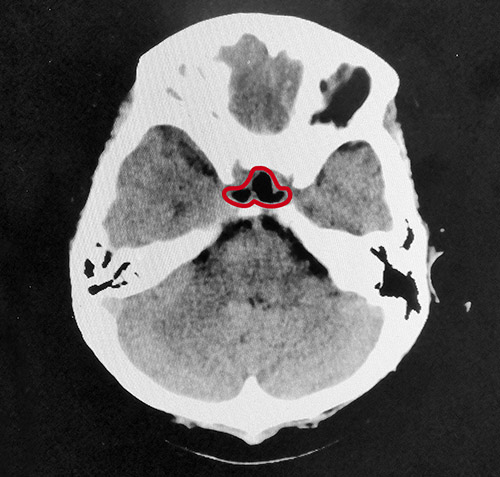

整个切除手术用时不到1小时,术中出血量很少,肿瘤切除干净。术后患者被医护人员唤醒,被安全送到重症监护室监护。经鼻蝶窦入路垂体瘤切除微创手术具有肿瘤暴露佳,创伤和危险性小,手术时间短、颅面外观无损伤,手术效果好等优点,但该手术方式对专家的技术水平也有着非常高的要求。

▲术后影像:肿瘤切除干净,鞍内脑脊液填充